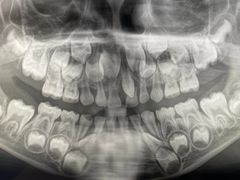

• 牙博士口腔品牌连锁(杨浦店)

• -牙博士口腔品牌连锁(杨浦店)